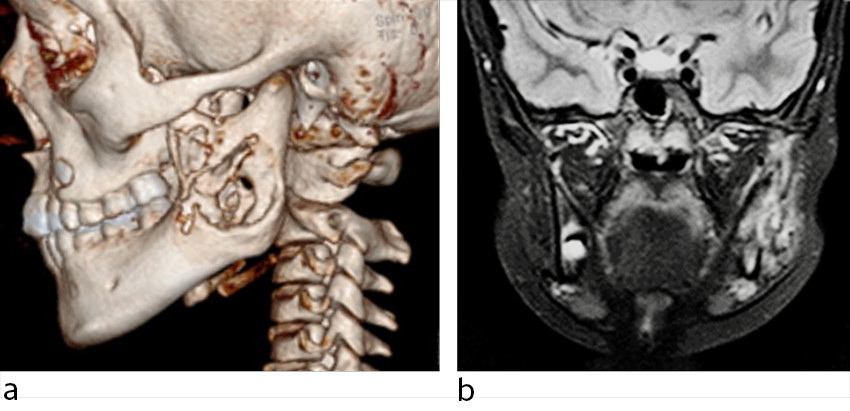

Ved klinisk undersøkelse observerte man asymmetri i ansiktet og en fast, lett palpasjonsøm hevelse på ca. 3 cm langs høyre underkjeve uten infeksjonstegn i huden eller tennene. MR- og CT-undersøkelse viste ekspandert ben med ødem i høyre underkjeve og kontrastoppladning i omliggende bløtvev (figur 3).